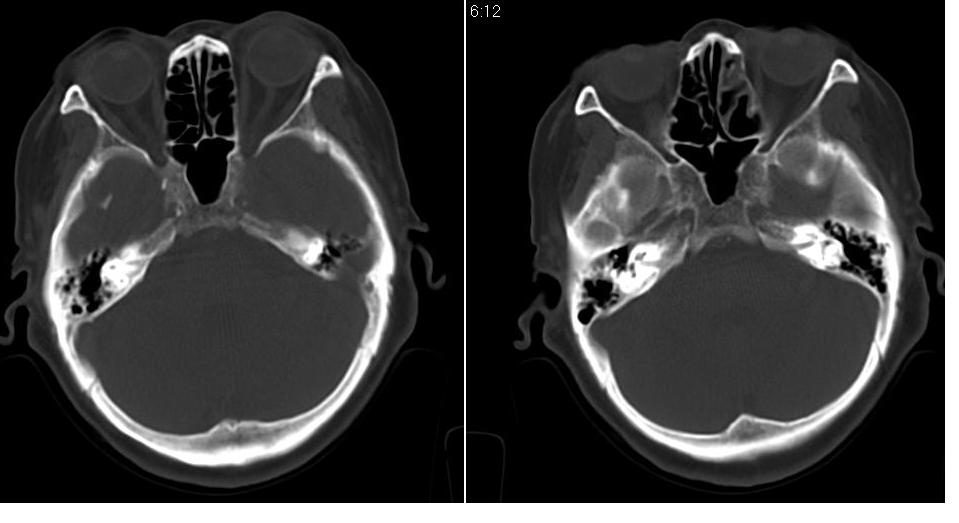

女 70岁,左侧上颌窦腔内肿物。

左侧颌窦内可见高密度影充填,窦壁增厚 考虑 左颌窦囊肿 慢性炎症

左侧上颌窦内软组织影,略呈膨胀性,窦壁骨质增生硬化,考虑为黏膜下囊肿.左侧筛窦炎

从病灶生长方式分析,更支持:上颌窦囊肿。

左侧上颌窦内软组织密度影,窦壁骨质增厚,密度增高,窦口扩大,考虑左侧上颌窦慢性炎症,息肉样变。

左侧上颌窦窦内可见高密度影充填,窦壁增厚,考虑左上颌窦窦囊肿,慢性炎症.